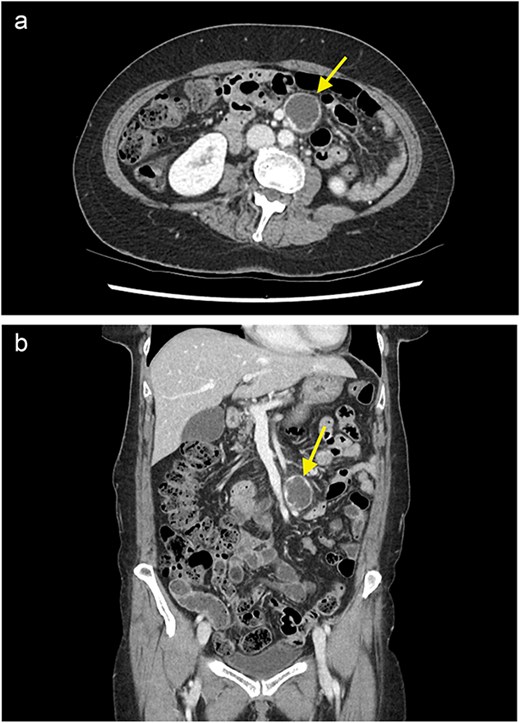

On examination, the patient was haemodynamically stable, and her abdominal exam and preliminary bloods were unremarkable. A computed tomography (CT) scan of the abdomen and pelvis with portal venous contrast revealed an ovoid lesion in the small bowel mesentery, adjacent to the superior mesenteric artery and vein (SMA/SMV) (Fig. 1). The lesion was peripherally enhancing, but centrally hypodense/cystic in nature and measured 32 × 28 mm. Differentials included a necrotic lesion. No other intra-abdominal or retroperitoneal masses were seen. The patient was admitted under the general surgical team for further investigation.

A contrast enhanced CT of the abdomen and pelvis (portal venous phase) with axial (a) and coronal (b) views demonstrating a cystic lesion in the small bowel mesentery (arrow).